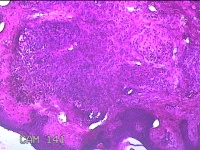

臀部肿物

性别

女

年龄

32岁

临床诊断

脂溢性角化病;皮肤感染

一般病史

颈部臀部丘疹数年。

标本名称

大体所见

灰白粉红色带皮肤样肿物1.8x0.5x0.2cm一个,表面糜烂。

图4